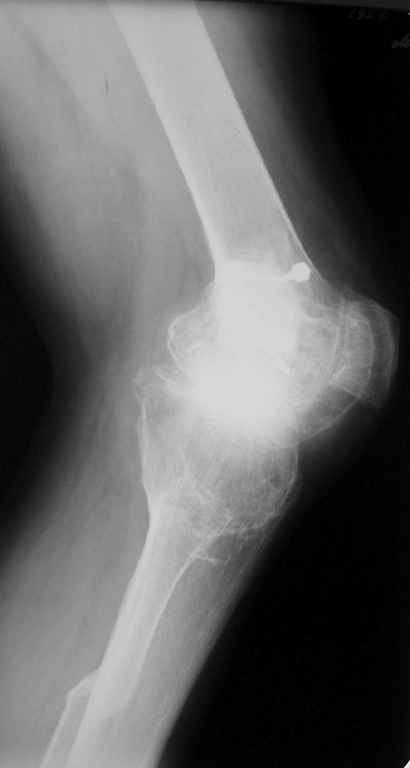

Пациент 59 лет, в 1982 году по поводу остеобластокластомы была выполнена частичная резекция проксимального отдела бедра с пластикой дефекта костно-хрящевым трансплантатом (моноблок)с фиксацией металлическими стяжками.

В последующем по поводу деформирующего артроза выполнена корригирущая остеотомия большеберцовой кости. Исход представлен на рентгенограмме. В настоящий момент пациента беспокоят боли в коленном суставе, деформация, и ограничение движений. Варусная деформация коленного сустава 20, движения сгибание 115, разгибание 150, ходит с тростью, выраженная хромота, работа не связана с физическими нагрузками. Правый коленный сустав без патологии. Уважаемые коллеги просим высказать своё мнение - артродез коленного сустава или эндопротезирование.